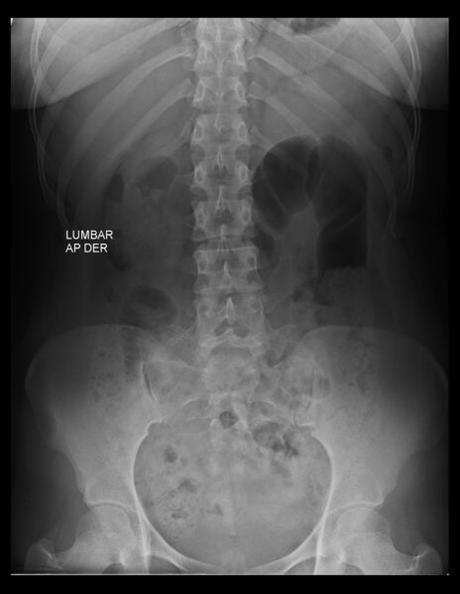

RADIOGRAFIA AP Y LATERALES DE COLUMNA LUMBAR

HALLAZGOS:

-Tejidos blandos, con densidad y morfología respetada, sin evidencia de lesiones.

-Columna vertebral, central. Sin listesis. Lordosis lumbar, con aumentos angulación.

-Cuerpos vertebrales con altura preservada, sin evidencia de lesiones líticas, blásticas o perdida de la contigüidad.

-Plataformas vertebrales, con adecuada densidad y morfología.

-Pedículos, laminas posteriores sin evidencias de lesiones líticas, blásticas o perdidas de la contigüidad.

-Apófisis transversas de L5, con fusión de apófisis derecha con sacro, y apófisis transversa izquierda con longitud mayor a 19 mm. Resto de apófisis espinosas, transversas y facetas sin evidencias de lesiones líticas, blásticas o perdidas de la contigüidad.

-Espacio intervertebrales, con adecuada amplitud.

-Neuro forámenes, con diminución de su amplitud en L5-S1, resto con adecuada amplitud.

OPINIÓN RADIOLÓGICA:

EL PRESENTE ESTUDIO RADIOGRAFICO, CON HIPERLORDOSIS LUMBAR.

SACRALIZACIÓN DE L5 CASTELLVI TIPO IV.

APARENTE ESTENOSIS DE NEURO FORÁMENES DE L5-S1.

CORRELACIONAR CON DATOS E HISTORIA CLINICA DEL PACIENTE.